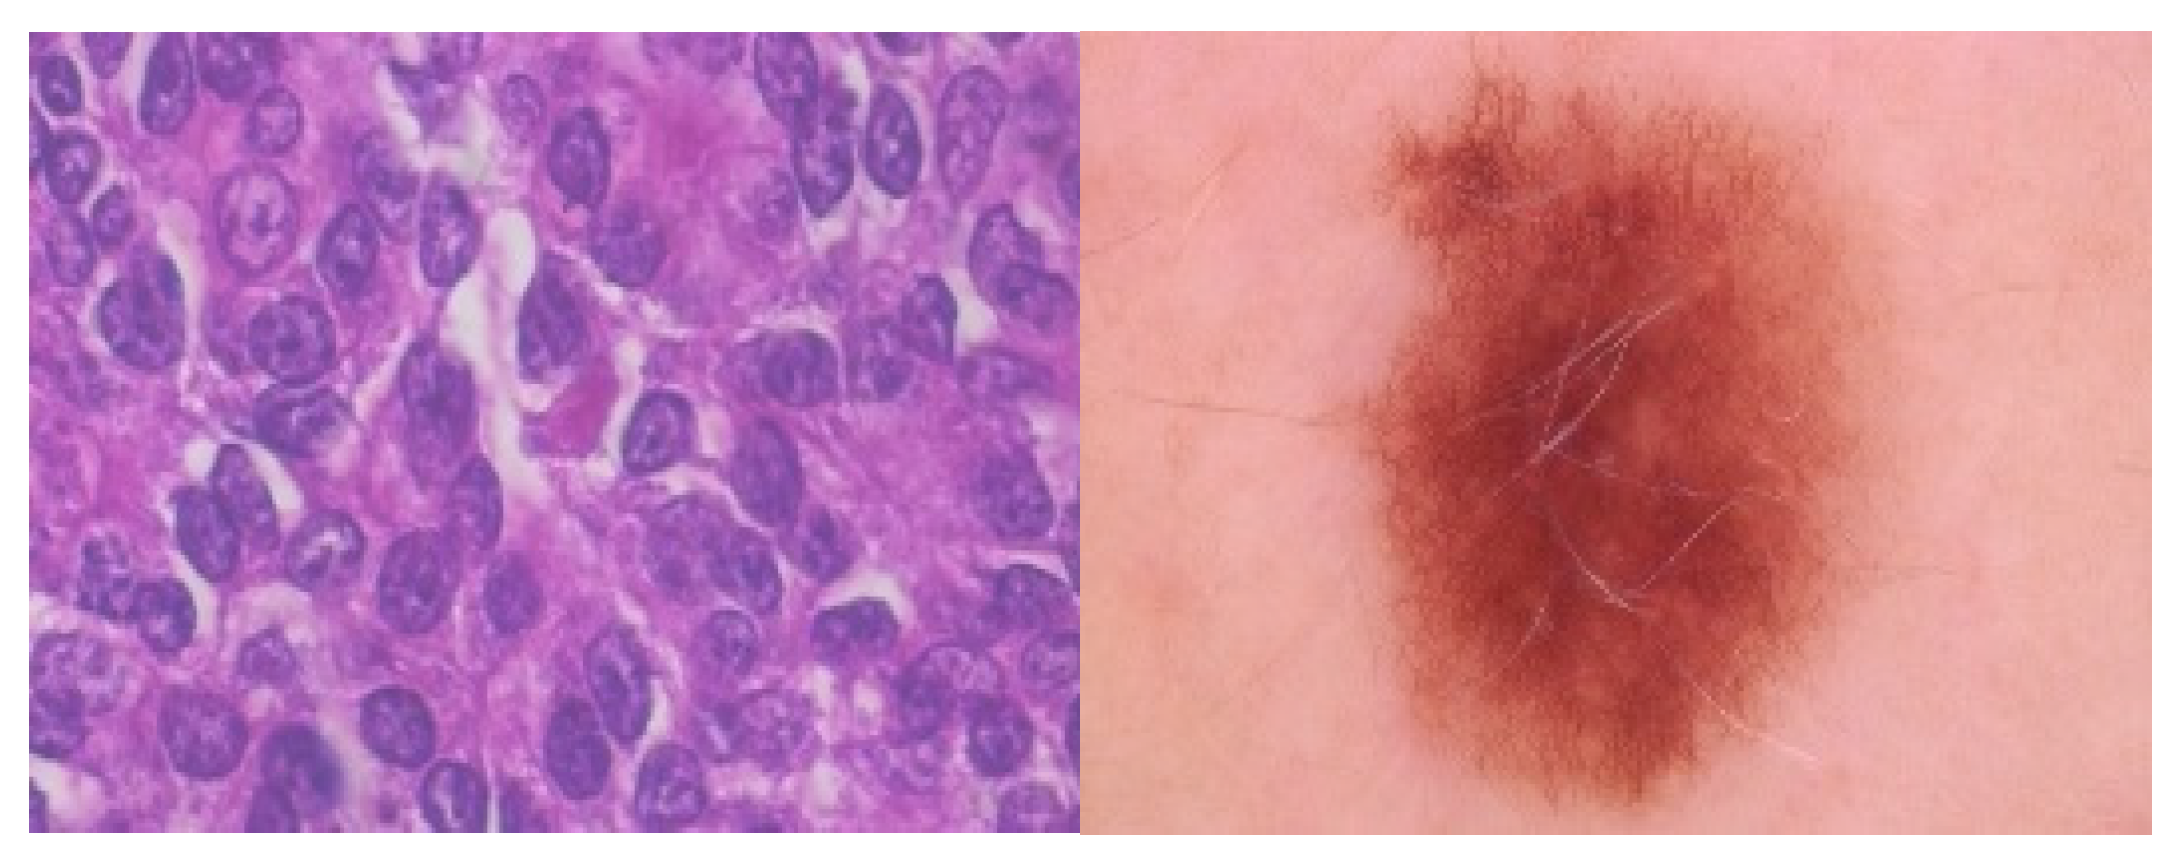

4.3.1. Dataset

- Spanhol, F.A.; Oliveira, L.S.; Petitjean, C.; Heutte, L. A Dataset for Breast Cancer Histopathological Image Classification. IEEE Trans. Biomed. Eng. 2016, 63, 1455–1462. [Google Scholar] [CrossRef]

- Al-Masni, M.A.; Al-Antari, M.A.; Choi, M.-T.; Han, S.-M.; Kim, T.-S. Skin lesion segmentation in dermoscopy images via deep full resolution convolutional networks. Comput. Methods Programs Biomed. 2018, 162, 221–231. [Google Scholar] [CrossRef]